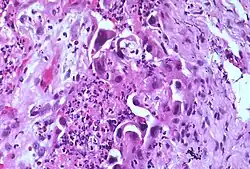

Atypia (from Greek, a + typos, without type; a condition of being irregular or nonstandard)[1] is a histopathologic term for a structural abnormality in a cell, i.e. it is used to describe atypical cells.

Features that constitute atypia have different definitions for different diseases, but often include the following nucleus abnormalities:[3]

- Enlargement

- Pleomorphism

- Nuclear polychromasia, which means variability in nuclear chromatin content.[4] Polychromasia otherwise refers to a disease of immature red blood cells.

- Numerous mitotic figures